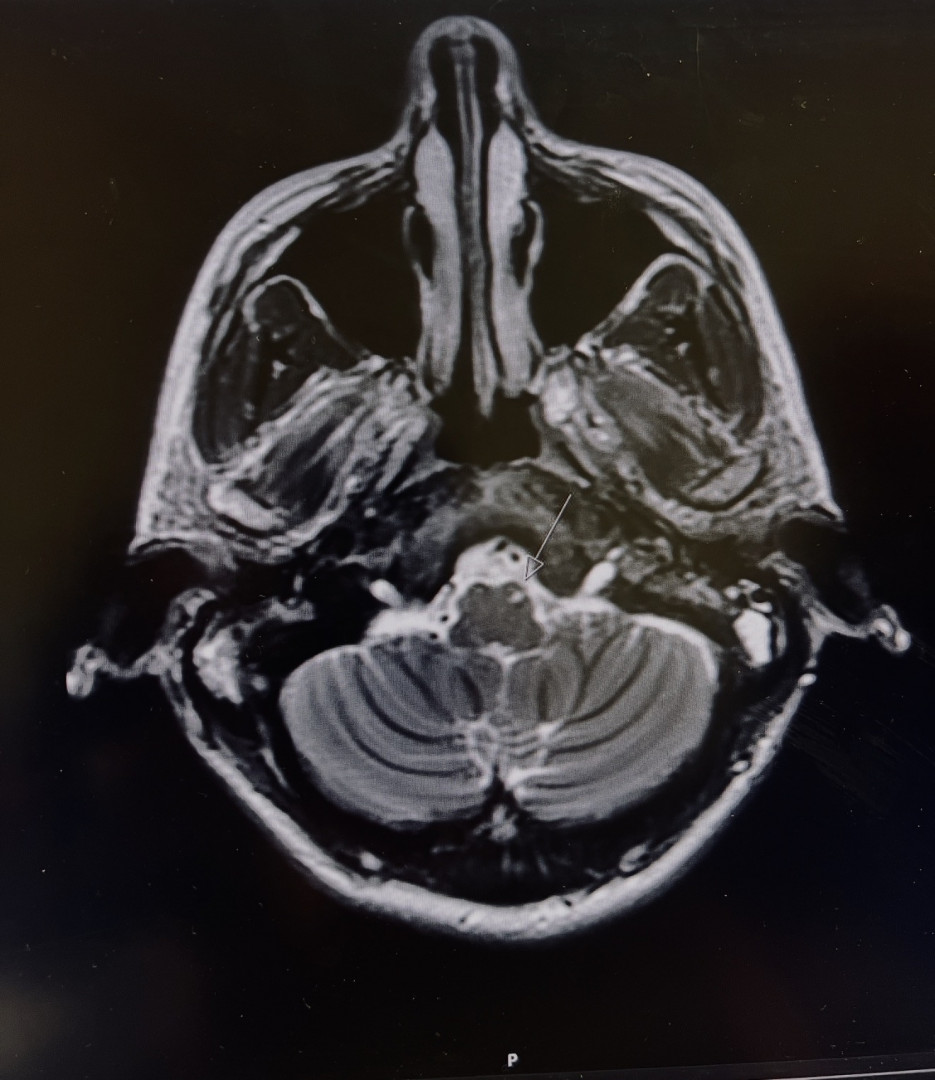

Survived a stroke & became an NPC competitor. I rebuilt my strength & identity. Proof that with faith & determination, women can rise again.